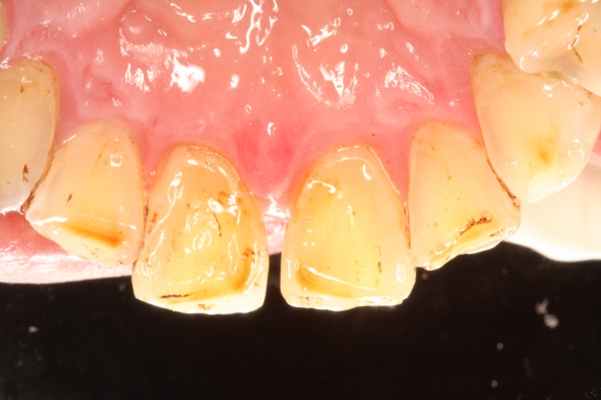

牙周炎圖片

牙周袋 (47)

牙周袋 (48)

牙周袋 (49)